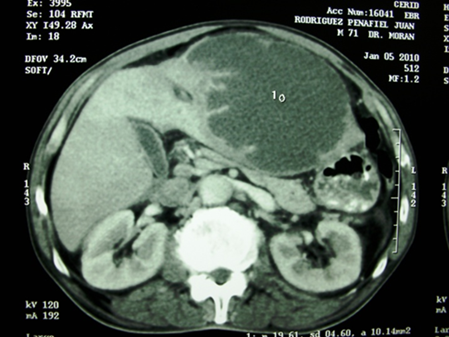

1. Absceso hepático

Ilustración 1 Tomografía con absceso hepático del lóbulo derecho

Fuente: Hospital de Especialidades Guayaquil “Doctor Abel Gilbert Pontón”.

Autor: Dr. Fernando Moncayo A.